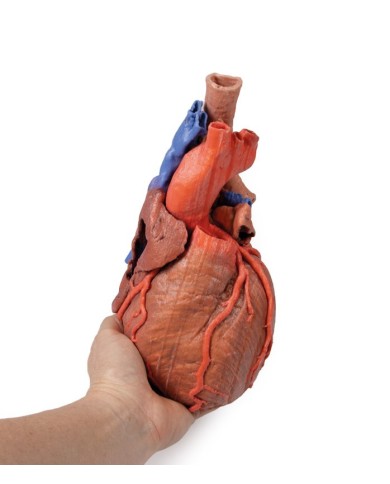

Modello di cuore di alta qualità scomponibile in 5 parti

Modello di cuore di alta qualità scomponibile in 5 parti

La parete anteriore del cuore è staccabile per poter vedere i ventricoli.

Realizzato in stampa 3D ad elevatissima risoluzione a colori.

Realizzato in stampa 3D ad elevatissima risoluzione a colori.

Realizzato in stampa 3D ad elevatissima risoluzione a colori.